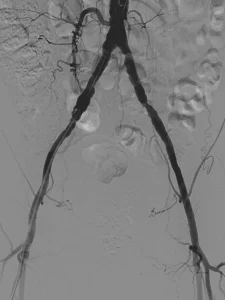

Imagen de una arteriografía mostrando las arterias principales en detalle

Arteriografía detallada de las arterias principales

Es un tipo de estudio con imágenes que se centra en las arterias. Se utiliza para diagnosticar y evaluar diversas condiciones vasculares, como aneurismas, estenosis, y malformaciones arteriovenosas. Los tipos de arteriografía incluyen: